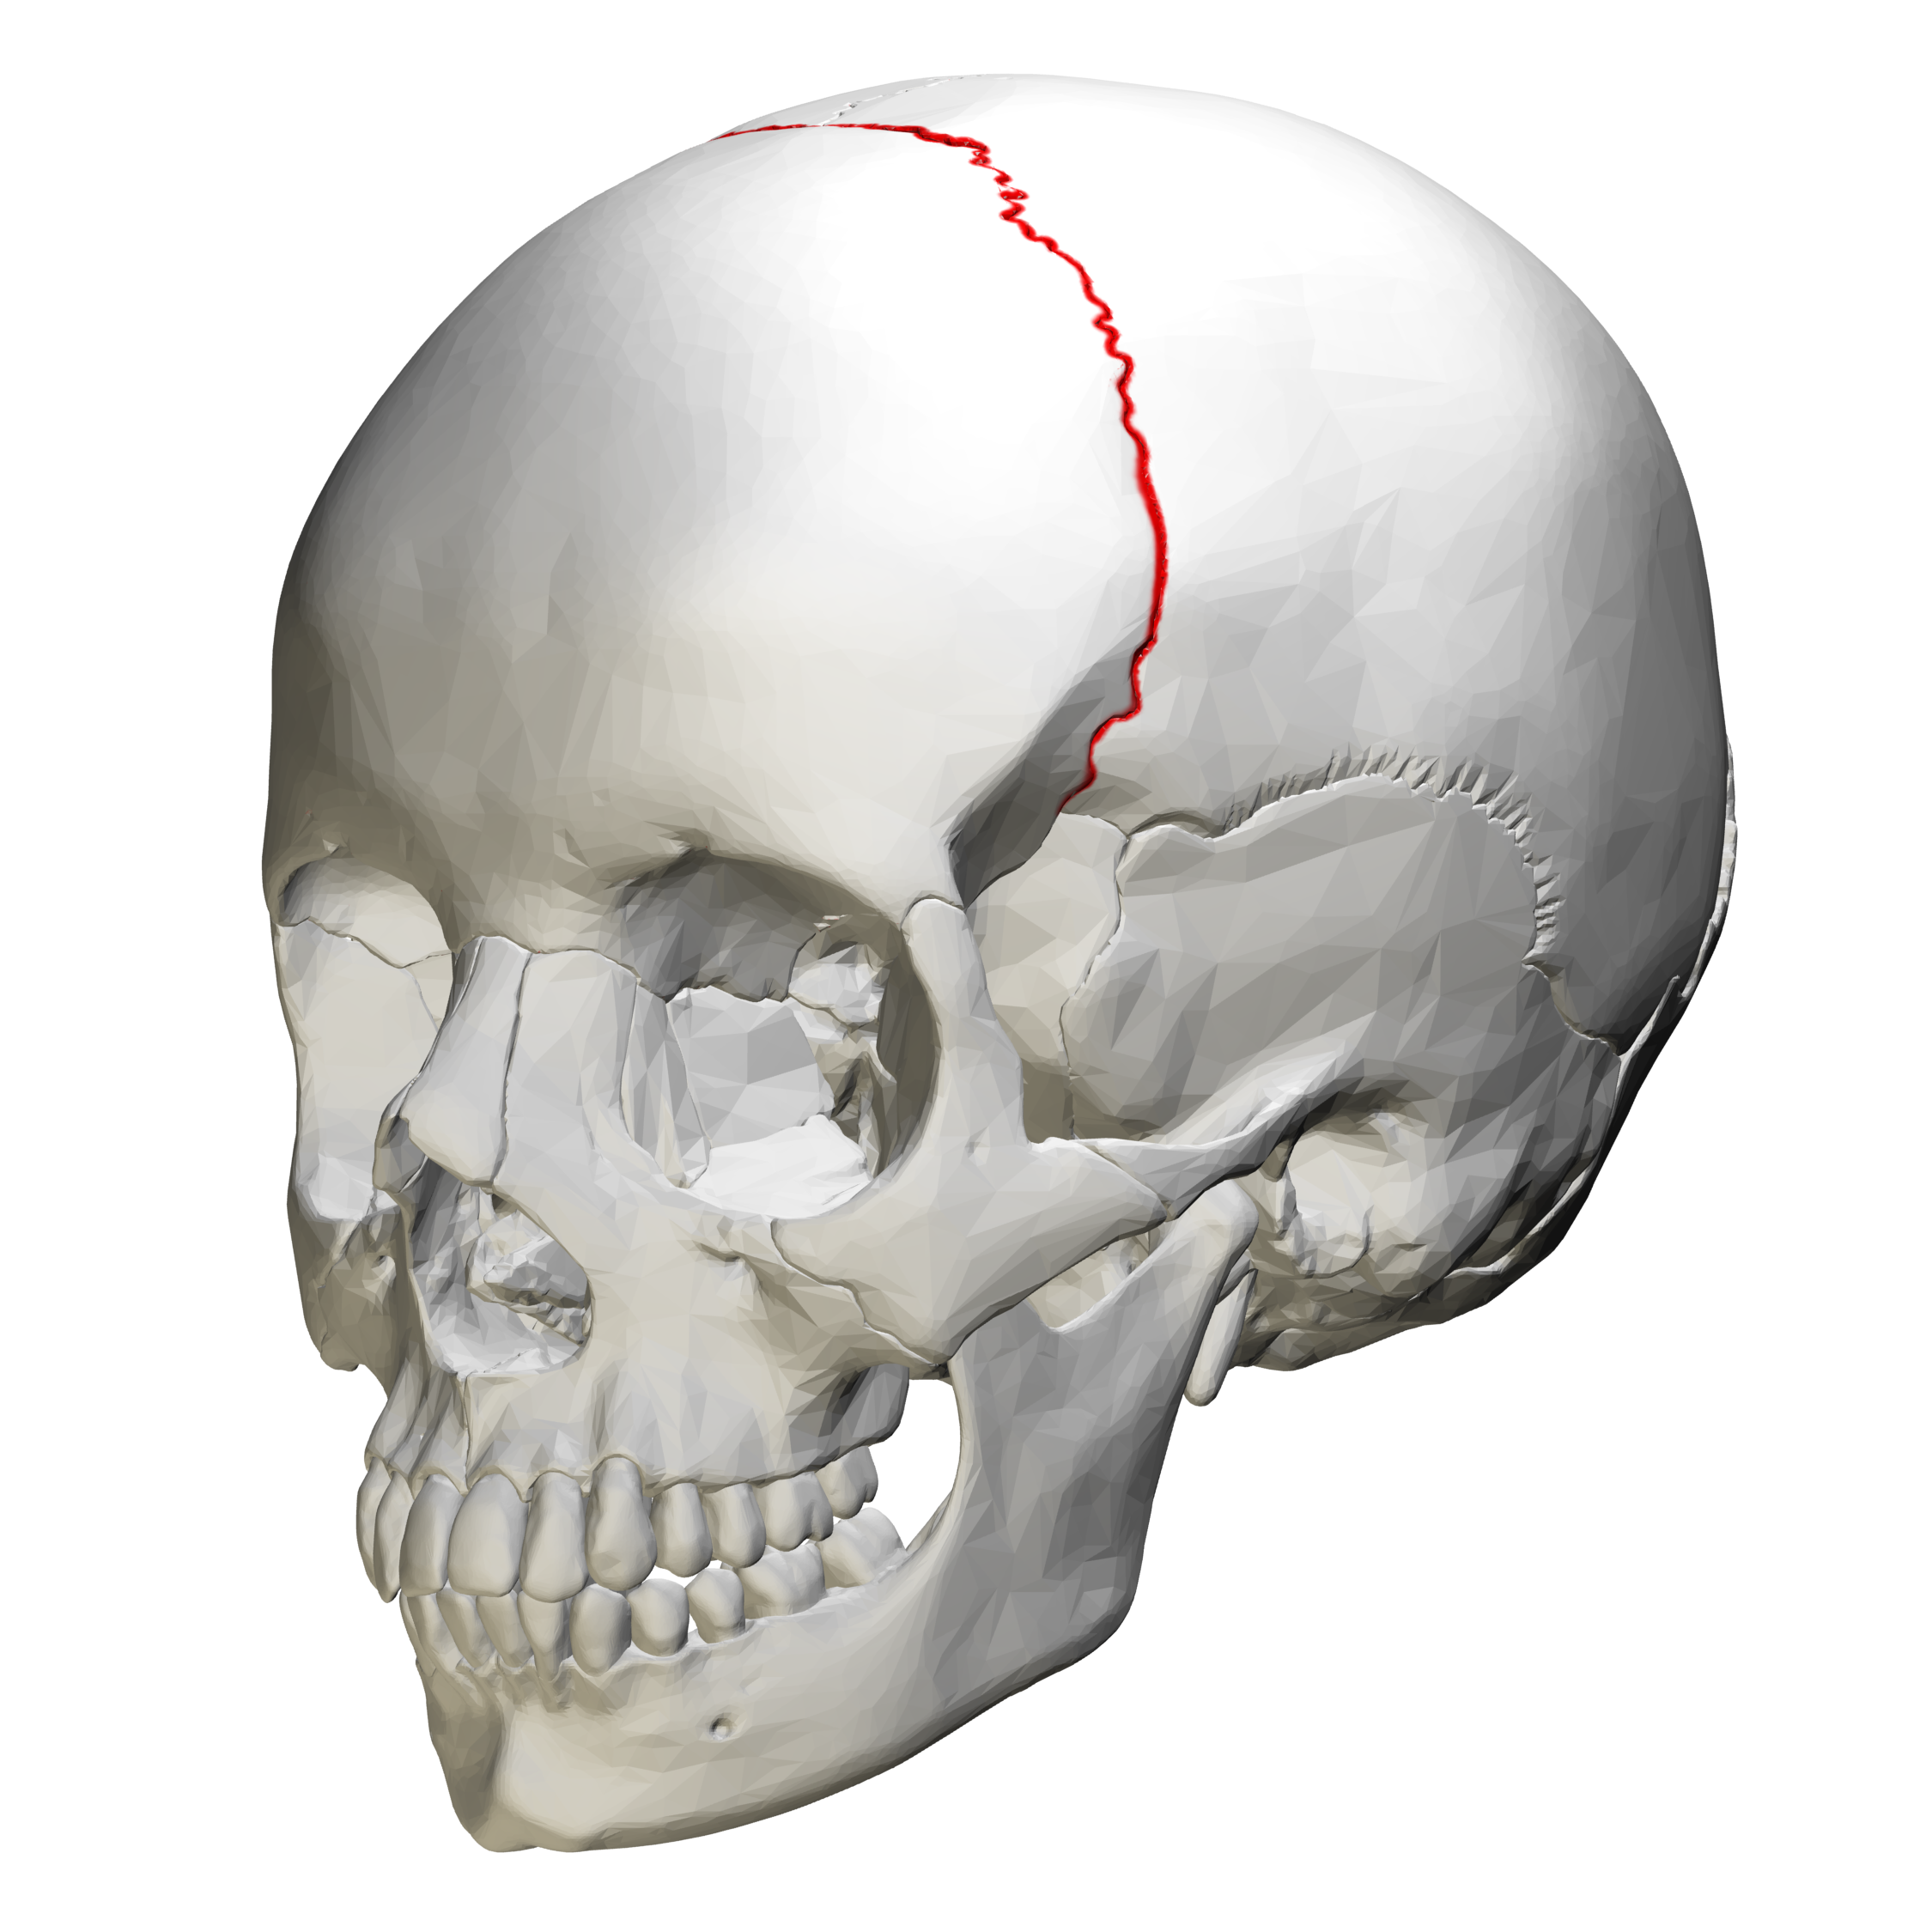

What are skull sutures?

Interlocking immovable joints of the skull

What suture is this?

Coronal Suture

Sagittal Suture

What do sutures tell you about the skull?

It shows that the skull is made up of more than one bone